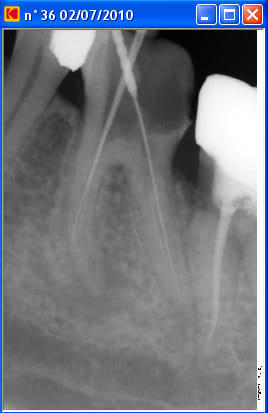

Un patient est venu pour la première fois en urgences pour douleur mandibulaire gauche: bilan radioclarté apicale sous la racine mésiale de 36, test percussion +++, ATB, disparition des douleurs à ce jour.

A la radio il y a une fausse route dans la racine mésiale.

J'ai réussi une fois à passer la fausse route et aller à l'apex à la lime 8. J'ai raclé au maximun les parois du canal.

Je remonte pour changer le diamètre de la lime et là le drame, plus moyen de descendre!!!

Petite précision: j'ai réussi à descendre dans le canal mésio vestibulaire, ça bloque dans le mésio lingual.